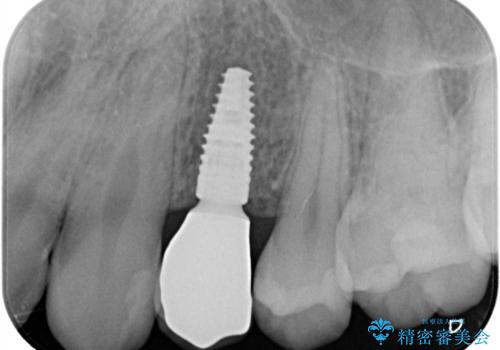

- 「歯がないので入れて欲しい」を主訴に来院された患者さんです。

虫歯がかなり進行していて根っこしか残っていない状態でした。日々の歯ブラシが上手く出来ていなくプラーク(細菌の塊)も溜まっている状態でした。

歯を保存するのは出来ないと診断し抜歯した後にインプラントで治療を行いました。

長い間虫歯を放置していたため、根っこだけになっている状態でした。このままでは被せ物を被せられないため抜歯を行い治癒を待った後にインプラントを埋入しオールセラミッククラウンで治療を行いました。